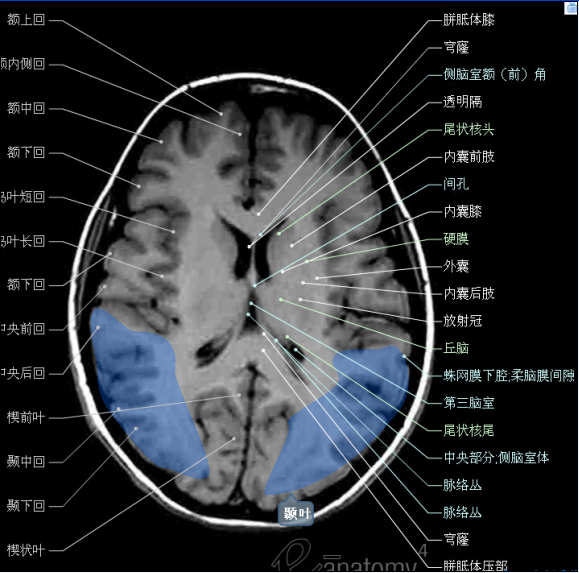

收藏高清颅脑断层解剖图谱

图片尺寸729x695